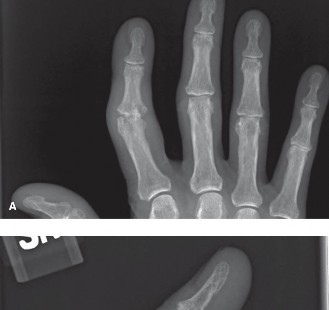

CASE 25 A 42-year-old man presents to the hospital with pain and swelling of th…